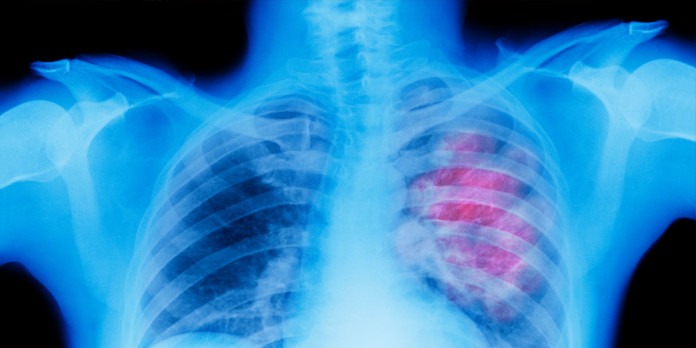

El cáncer de pulmón – la principal causa de muerte por cáncer – puede permanecer escondido en el interior del cuerpo por más de 20 años antes de repente convertirse en un cáncer de rápido y agresivo crecimiento, los investigadores han descubierto.

Un estudio reciente, llevado a cabo por científicos de Cancer Research del Reino Unido y publicado en la revista Science, revela que después de la falla genética inicial que causa cáncer en el paciente, la enfermedad puede permanecer latente y sin ser detectada durante un largo periodo de tiempo sólo para convertirse agresivamente activa cuando se activa por nuevos errores genéticos adicionales.